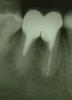

gorelovea Опубликовано 19 апреля, 2011 Поделиться Опубликовано 19 апреля, 2011 Пациентка С. 29 лет пришла с направлением на удаление 46 зуба. После консультации с ортопедом зуб решили сохранить.Перепломбировал корневые каналы, заапикально вывел "Vitapex" и запломбировал эндометазоном с гуттаперчей(на тот момент не было ни эндомотора, ни ультразвука).Далее провёл операцию премоляризации(разъединение), через 3-4 недели ортопед изготовил двевкладки и покрыл их металлокерамической коронкой.Через год сделали Rg-контроль. Зуб не беспокоил, в периапикальных тканях изменения уменьшались.Месяц назад сделали Rg-контроль(прошло 3 года). Зуб не беспокоит, в периапикальных тканях изменений нет. Ссылка на комментарий

Kivilgar Опубликовано 19 апреля, 2011 Поделиться Опубликовано 19 апреля, 2011 (изменено) Месяц назад сделали Rg-контроль(прошло 3 года). Зуб не беспокоит, в периапикальных тканях изменений нет. А мне видится, что патология в периапексе сохранена. И с костью вокруг корней проблемы. Все равно ждет удаление. Изменено 19 апреля, 2011 пользователем Kivilgar Ссылка на комментарий

pascal Опубликовано 21 апреля, 2011 Поделиться Опубликовано 21 апреля, 2011 А на втором снимке за верхушку эндометазон так выведен?? специально?? Почему имплант не захотели? Зубки три года то ещё простоят, но условия для адекватного протезирования уже уйдут Ссылка на комментарий

gorelovea Опубликовано 24 апреля, 2011 Автор Поделиться Опубликовано 24 апреля, 2011 А на втором снимке за верхушку эндометазон так выведен?? специально?? Почему имплант не захотели? Зубки три года то ещё простоят, но условия для адекватного протезирования уже уйдутЗаапикально выведен Vitapex. Ещё не известно сколько лет простоит имплант. А на тот момент у нас ставили только Новокузнецкие цилиндры с памятью формы. Ссылка на комментарий

pascal Опубликовано 25 апреля, 2011 Поделиться Опубликовано 25 апреля, 2011 Заапикально выведен Vitapex. Ещё не известно сколько лет простоит имплант. А на тот момент у нас ставили только Новокузнецкие цилиндры с памятью формы.Имплант простоит долго, просто надо иметь на примете хорошего имплантолога. И если даже у Вас ставят только Новокузнецк, направте в другой город , изготовив временную конструкцию например адгезивную. А так - вы старались, но очаги хронической инфекции остались, а в бифуркации даже увеличились. не надо эксперементировать, всё давно это до нас сделано Ссылка на комментарий

Каплан Опубликовано 5 февраля, 2014 Поделиться Опубликовано 5 февраля, 2014 Заапикально то зачем? Стечение обстоятельств или намеренно?Игорь, я думаю мы теперь никогда об этом не узнаем. А вообще, последняя манипуляция, которую я бы делал. Тут вообще очень показательно. За 3 года кость убежала по фуркации Ссылка на комментарий

Kolchanov Опубликовано 5 февраля, 2014 Поделиться Опубликовано 5 февраля, 2014 Прикольный случай какой! Только надо, чтобы ортопеды из ГОСа не видели У нас любят подобную х-ню восстанавливать. Жаль, что автор давно не появляется на форуме. Было бы интересно увидеть продолжение. За 3 года кость убежала по фуркации На биологическую ширину убежала. 2 Ссылка на комментарий